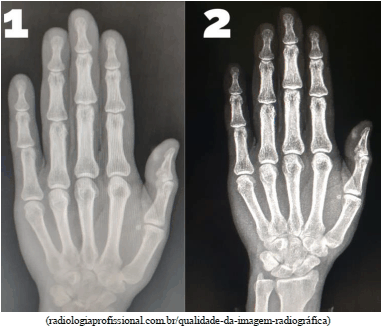

O fator de Miliamperagem por Segundo (MAS) determina o tempo em que o corpo está sendo penetrado pela radiação modificando a densidade. A partir da imagem 1 e 2 determine a afirmação verdadeira na sequência.